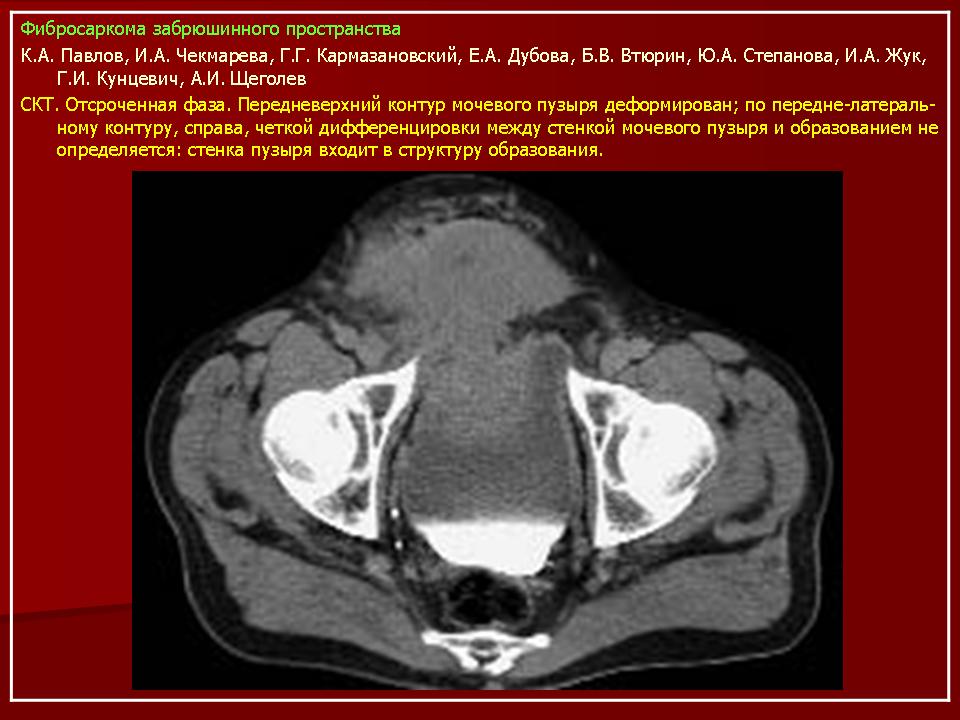

Онкология. Фибросаркома забрюшинного пространства. +

Фибросаркома забрюшинного пространства.